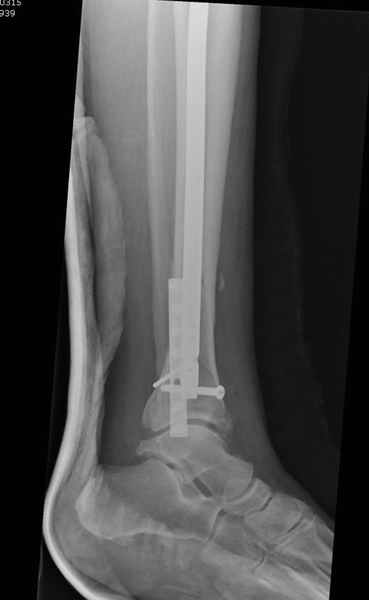

Здесь мы использовали новый Synthes Nail с дополнительными дырками, в проксимальной части 4: по две косых и поперечные (один стандартный а другой динамический), в дистальной части две поперечные, прямая и косая. Вес больного более 120 кг, нагрузку начнем через месяц.

Получилось красиво, поздравляю. Вверху можно было ограничиться одним винтом во фронтальное статическое отверстие, зачем два 45-градусных?

При такий спирали задний край tibia может быть сломан - нет ли этого в данном случае? На всякий случай можно было ввести 1-2 винта 4,5 мм спереди назад мимо гвоздя. Хотя самый дистальный блокирующий винт, возможно, зацепил этот отломок. А какой тут диаметр гвоздя и locking винтов?

DK> косая. Вес больного более 120 кг, нагрузку начнем через месяц.

Если там и правда сломан задний край, то лучше с нагрузкой подождать, даже будь больной полегче.